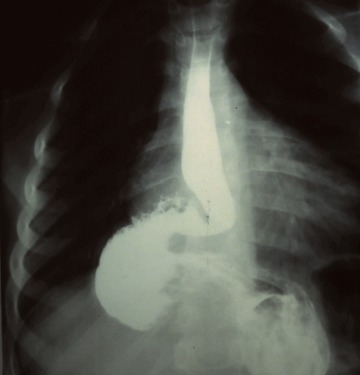

위조영술 검사는 바륨이라는 하얀 액체를 마시고 그 액체가 식도를 타고 내려가면서 위에 쌓였을 때 몸을 이리저리 뒤집어가면서 그 흑백화면을 보면서 읽어내는 검사방법입니다.

바륨현탁액, 요오드제제를 이용해 위의 이상 유무를 검사합니다. 이 용액은 X선 투과가 잘 안되는 물질로 이 용액을 마시고 X선이 발생되는 기계 위에서 몸을 이리저리 돌려가면서 검사를 받습니다. 기계가 알아서 돌아가는 것이 아니라 사람이 직접 그 기계 위해서 몸을 움직여 줘야 합니다.

X선이 발생하는 기계 위에 있으므로 그 방사선이 몸을 투과하므로 미량의 방사선 피폭이 있다는 것은 인지해야 합니다. 위조영술 검사방법은 위를 풍선처럼 팽창시켜 위벽에 조영제 코팅해 위벽 병변 유무를 검사하는 방법과 위가 팽창하지 않은 상태에서 위를 조영제로 채워 검사하는 두가지 방법이 있으며 일반적으로 두가지 다 시행해야 위벽과 안을 다 검사 할 수 있습니다.

하지만 위조영술 검사 장점도 분명히 존재합니다. 이는 그래도 위내시경 검사처럼 굵은 카메라를 삼켜야 하는 불편함이 없으며 노인이나 기저질환이 있는 환자도 위 검사를 받을 수 있고 식도에서 위 그리고 십이지장으로 이어지는 위장관의 전체적 모양과 연동운동을 관찰 할 수 있다는 점입니다.